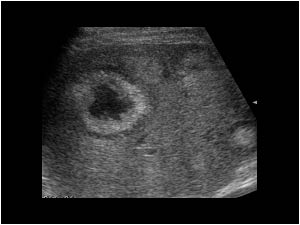

Как выглядят метастазы на УЗИ? На мониторе ультразвукового аппарата метастатическая опухоль просматривается в виде небольшого эхогенного участка с четко выраженной границей .

Как на УЗИ выглядят метастазы в печени . Местоположение раковых очагов представляется на экране в виде очаговых паренхиматозных изменений .